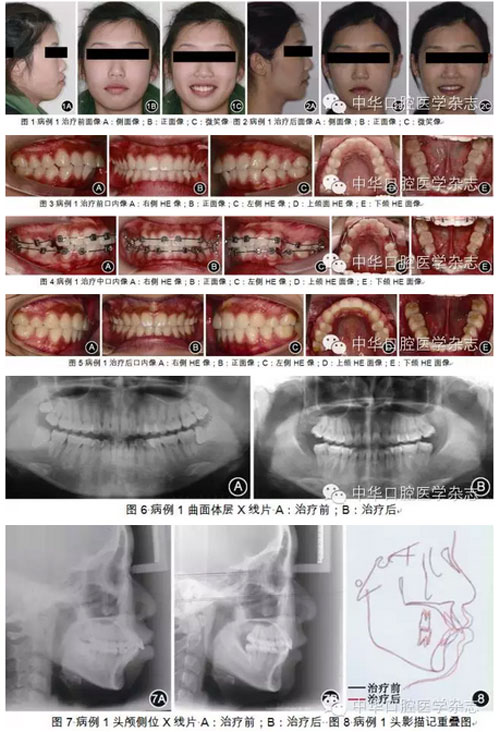

長(zhǎng)、露齦笑、唇肌閉合不良等后果,使面形無(wú)法有效改善。因此,對(duì)于前突的Ⅱ類錯(cuò)HE患者,為了達(dá)到控制上頜前牙-牙槽骨(或上頜骨)并使下頜向前向上變化的目的,必須:①先使用向上向后的矯治力遠(yuǎn)中直立下頜磨牙,將下頜前牙內(nèi)收直立于基骨上,同時(shí)維持或適度后傾上頜磨牙,使上頜前牙向上向后移動(dòng);②用使下頜向前向上的矯治力使下頜產(chǎn)生相應(yīng)反應(yīng)。垂直向控制必須貫穿整個(gè)治療過(guò)程,即必須控制磨牙的垂直位置,同時(shí)控制下頜平面、腭平面和HE平面。